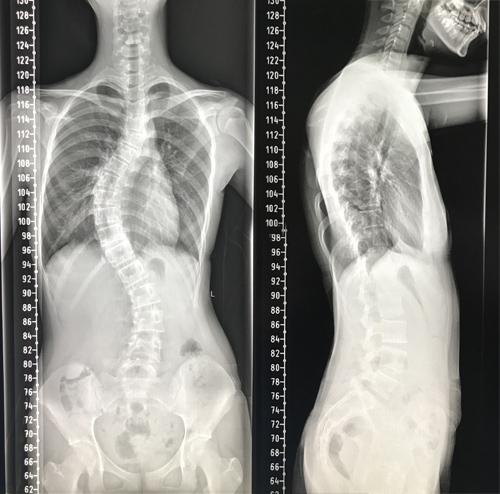

患者小冰今年13岁,4个月前家属发现小冰肩背部明显不对称,严重影响美观,且无法平卧入睡,经多方咨询,慕名来临床医学院/附属医院骨三科就诊。专科检查发现患者脊柱呈明显S型弯曲,躯干向右侧倾斜,双肩不等高,剃刀背畸形,主胸弯Cobb角度达60°,脊柱畸形较为严重。该院骨三科朱述浪主任带领脊柱外科团队,详细讨论了小冰的病情。